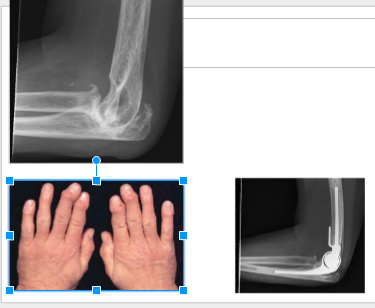

Dupuytren’s Syndrome

What is this?

Arthritis